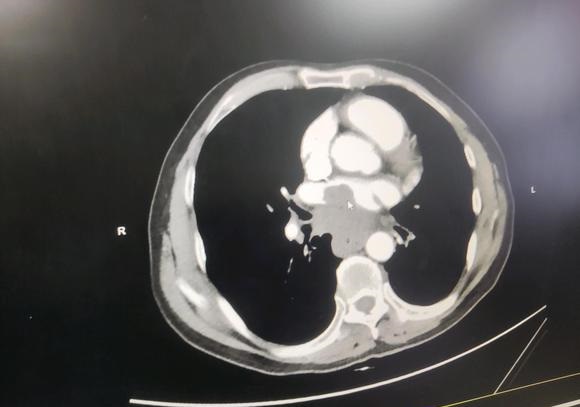

为自己,拼一次 02021-12-22 患者

为自己,拼一次 02021-12-22 患者 -